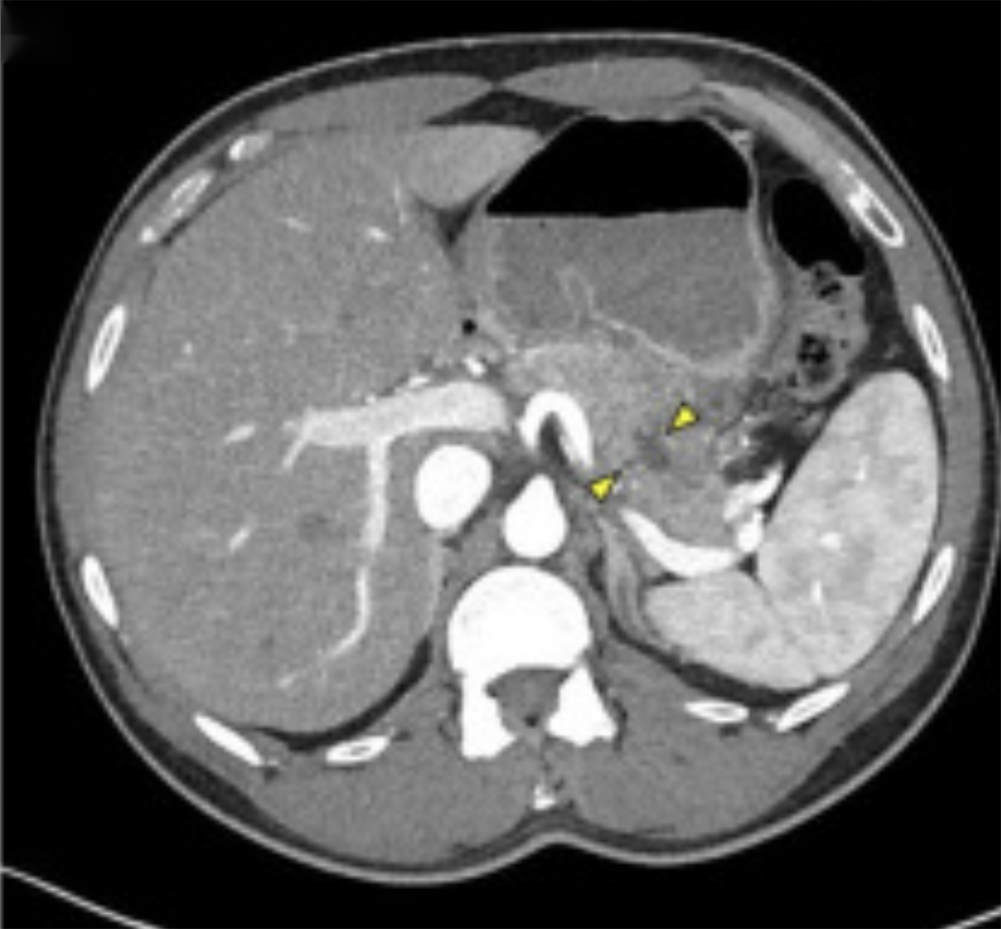

实验室检查:再次显示乳糜血,血红蛋白水平为13.8g/dl,血小板计数为193×109/L,白细胞计数为6.7×109/L。电解质水平在正常范围内,除了碳酸氢盐水平为20mmol/L(22至29mmol/L);其血浆葡萄糖水平为97mg/dl,肌酐水平为0.87mg/dL。肝功能检测显示正常,血清脂肪酶值为107U/L(13至60U/L)。腹部/骨盆CT扫描显示胰腺尾部新出现一个1cm的非增强低密度区(图2)。这究竟是怎么引起的?

图2.腹部/骨盆CT结果,黄箭头之间显示的为1cm的不增强低密度区域